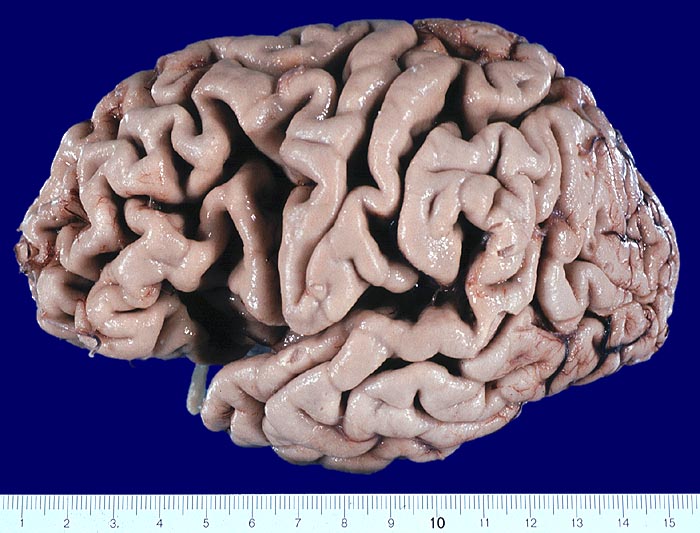

PathoPic ID 4036 - Morbus Alzheimer

Morbus Alzheimer

Ausgeprägte Atrophie der Grosshirnrinde mit Verschmälerung der Gyri und konsekutiver Verbreiterung der Sulci.

Demenz

Makroskopie

83